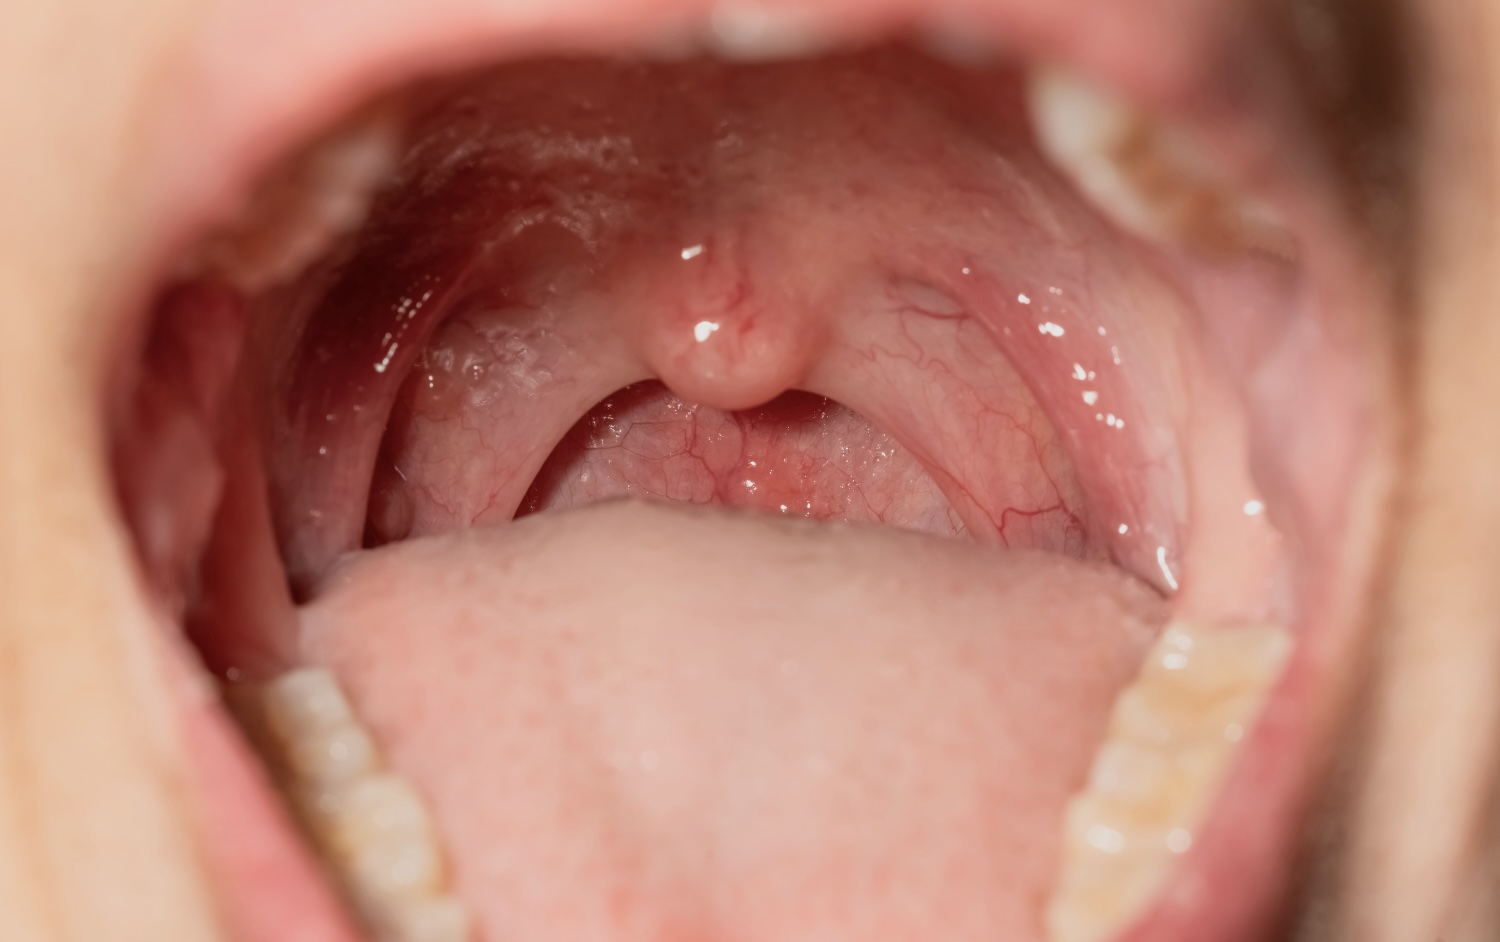

Persistent mouth breathing and snoring in children can signal airway obstruction, often from enlarged adenoids and tonsils. Early care can protect sleep, learning, and facial development.

Viral versus bacterial tonsillitis, red flags, and how ENT care fits when infections keep coming back.